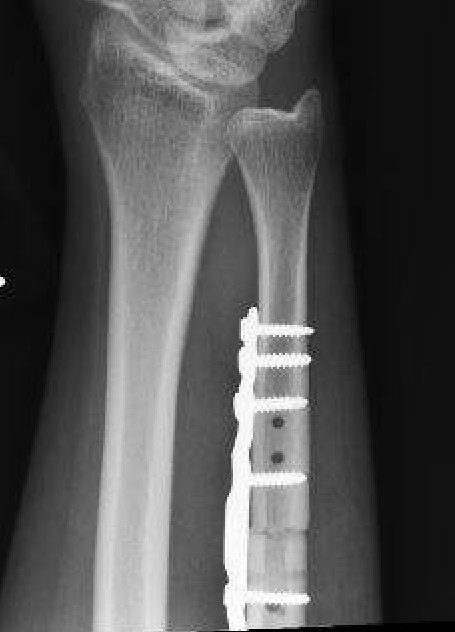

Ulna shortening osteotomy

Technique

Approach to ulna

- between ECU and FCU

- can use cutting jigs

- resect 2 - 6 mm of ulna based on xray templating

- compression plate